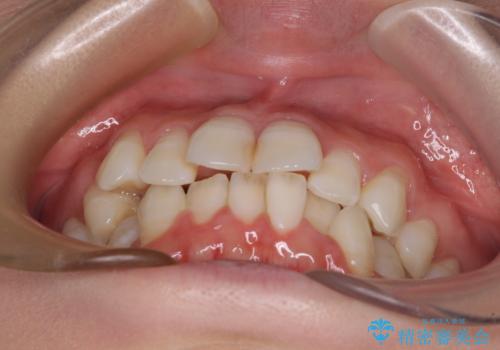

- 上下前歯のデコボコを改善したいとのことで来院された患者様です。

初めの1年くらいは何とか頑張って装着してくださいましたが、途中から変化をあまり感じられなくなり、日々の装着時間は徐々に短くなってしまいました。

前歯のデコボコはもっと改善できましたが、3年半が経過し、初診時と比べたら大幅に良くなったとのことで終了することとなりました。